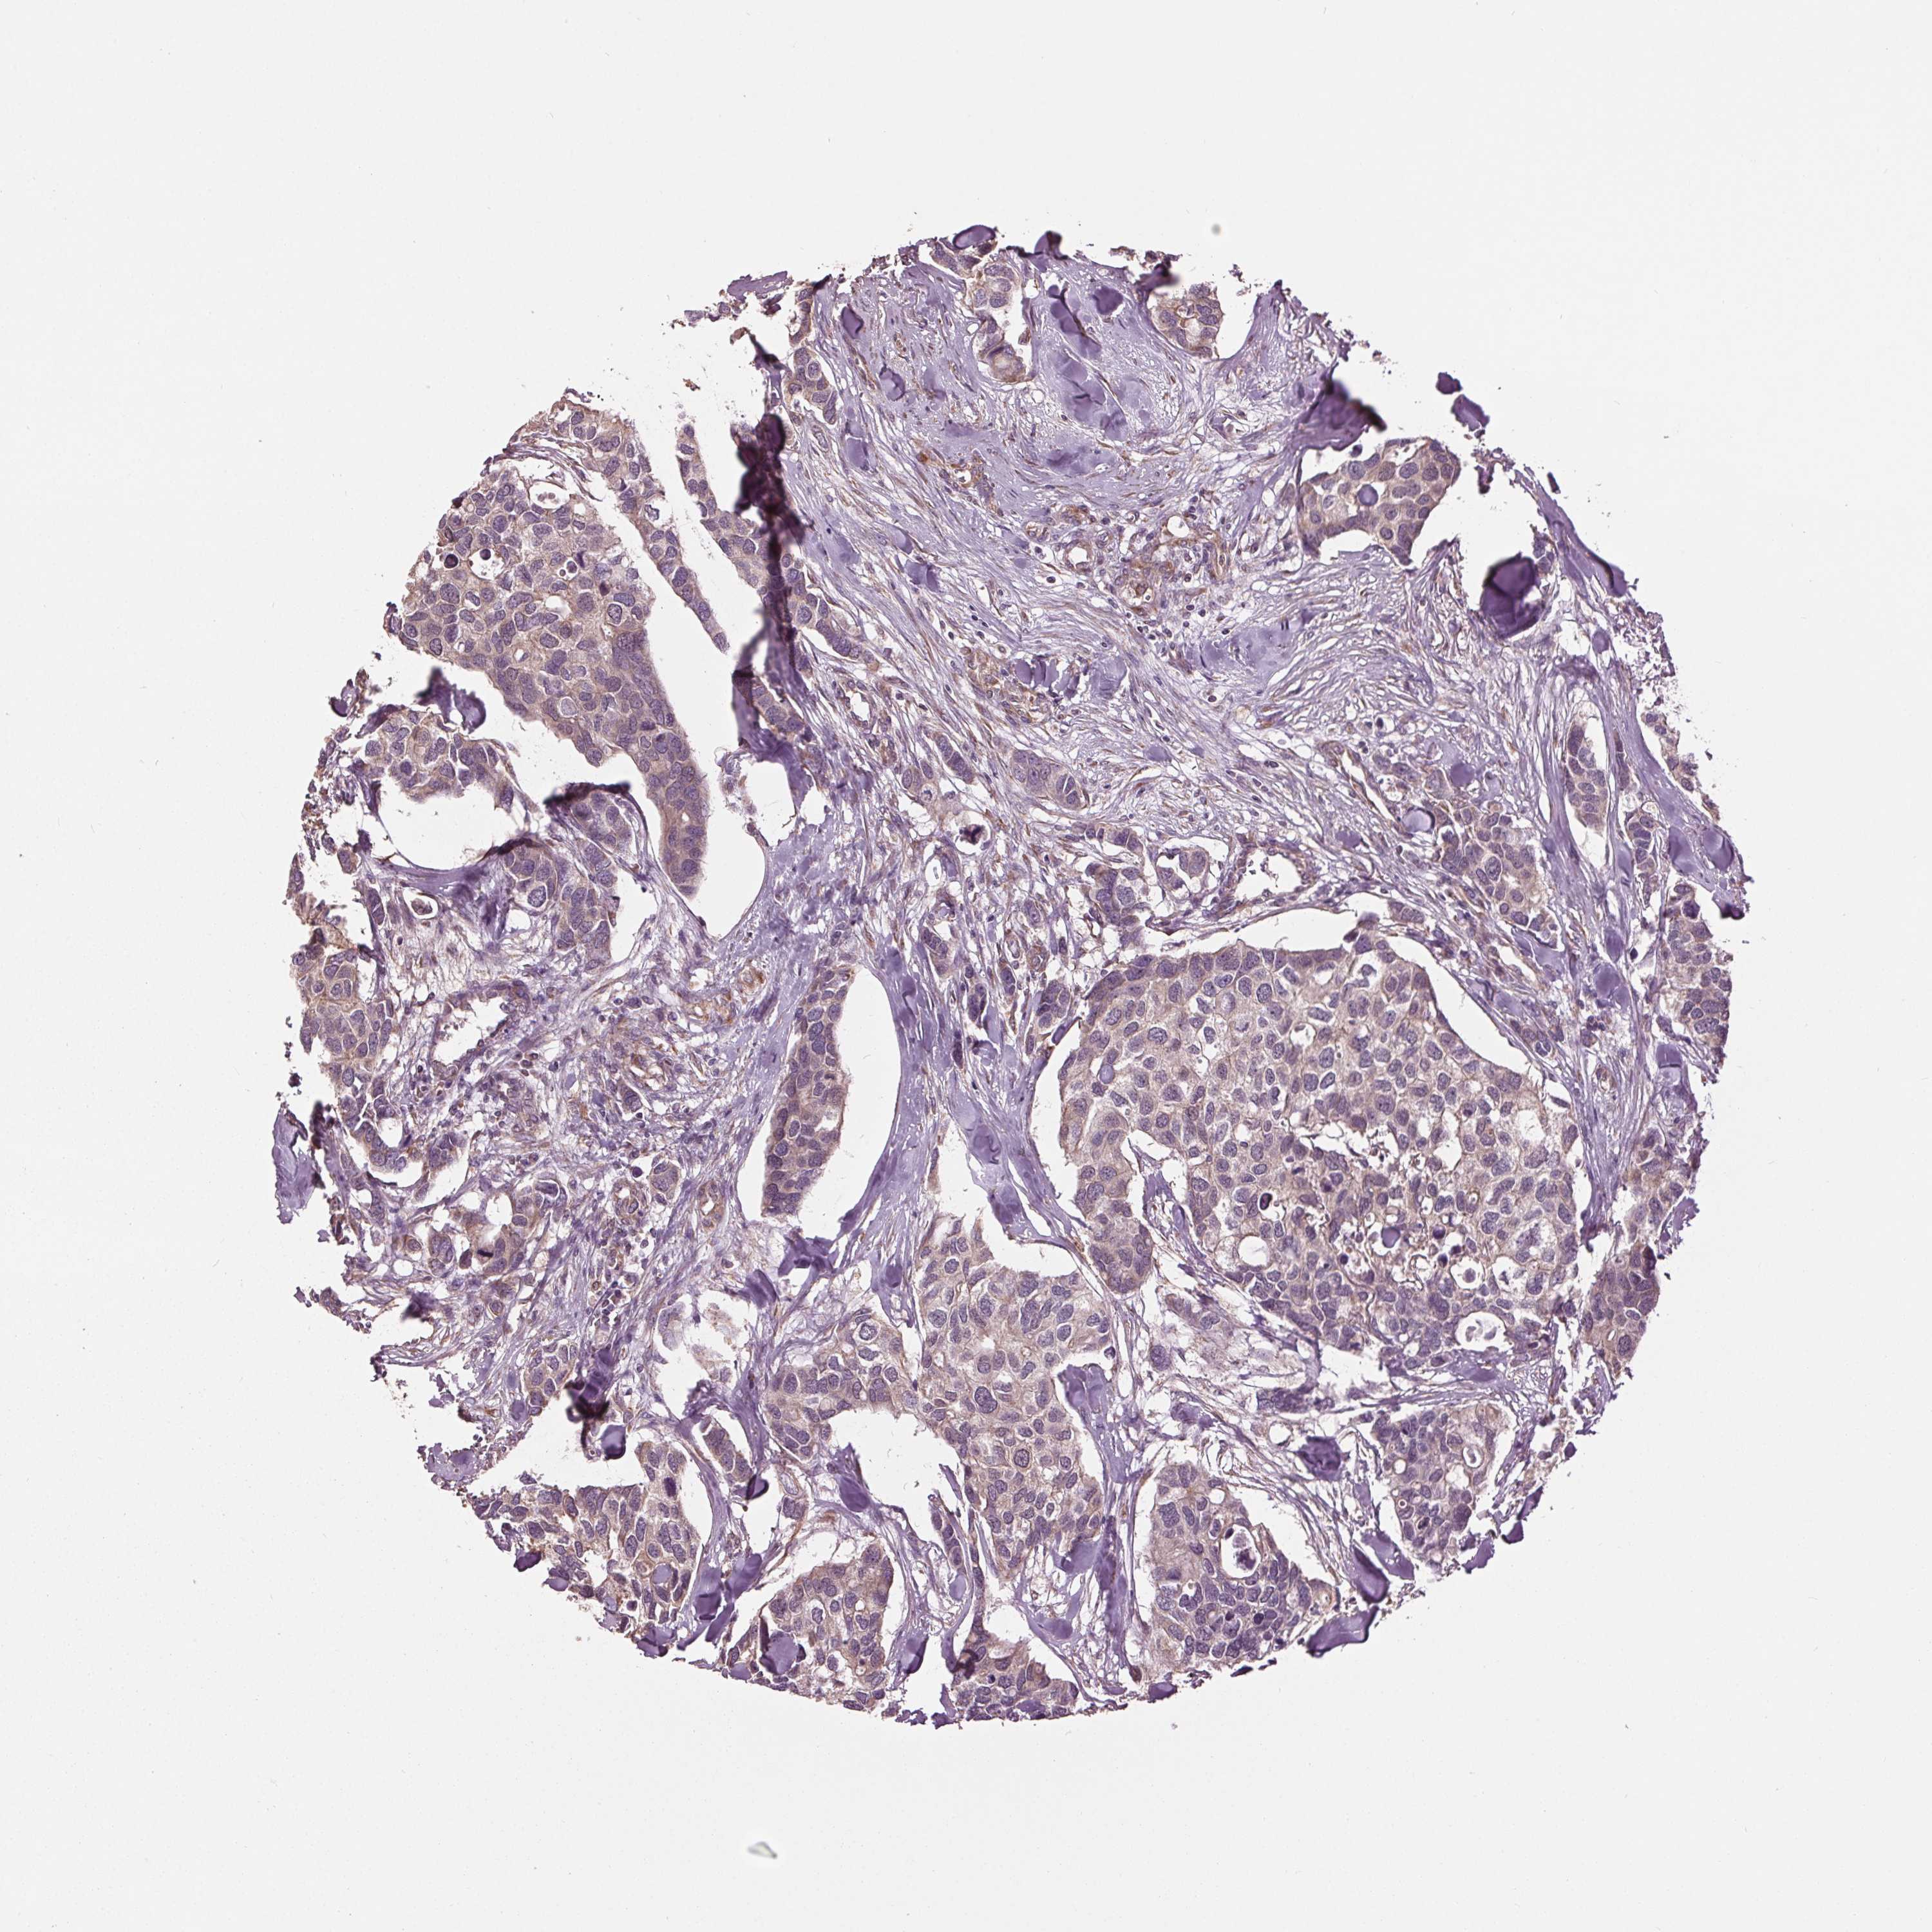

CANCER BREAST CANCER Show tissue menu

BRCA TCGA BRCA VALIDATION PROTEIN EXPRESSION